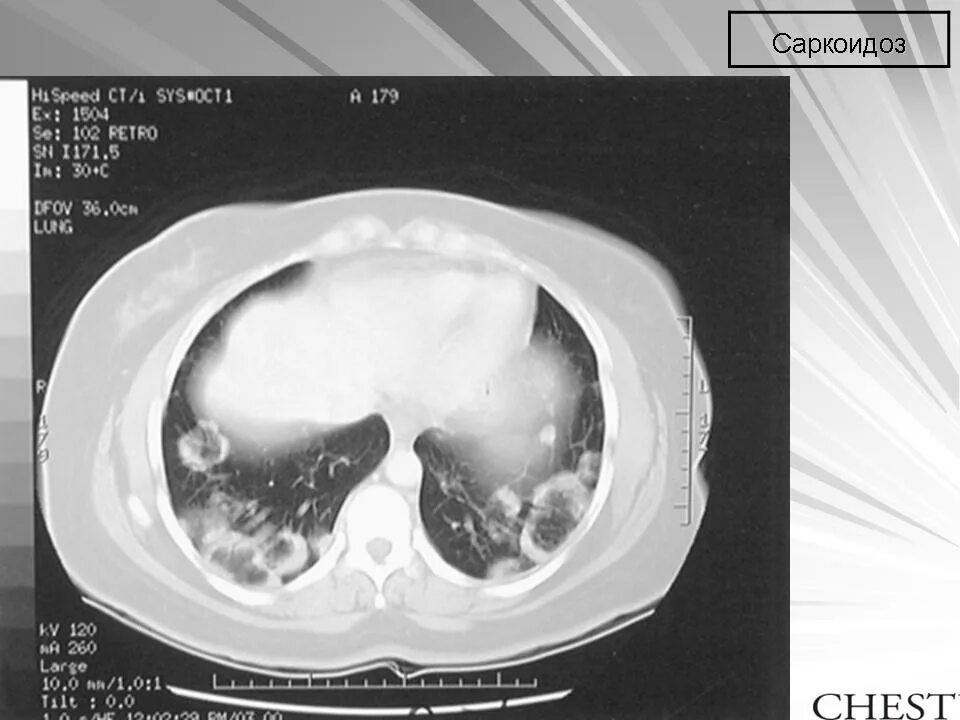

Саркоидоз 1